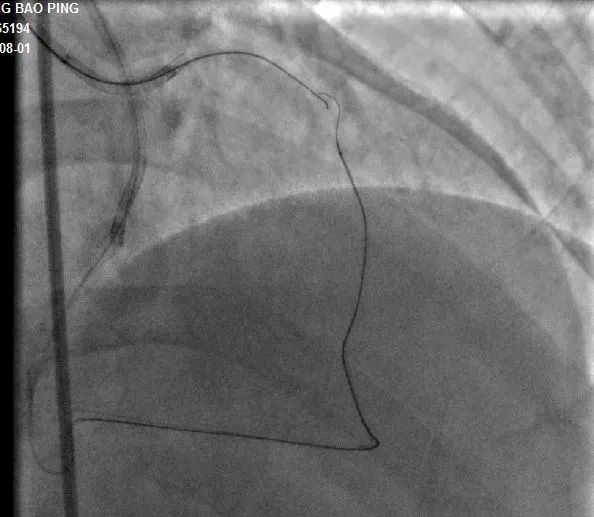

近日 长治二院心血管内科团队 成功完成 一例高难度 逆向CTO(冠状动脉慢性完全闭塞病变)介入手术 该项技术的成功突破 标志着医院心血管内科 冠脉介入技术跃 上了一个新的台阶 ...... 病例分析 手术现场 手术过程:7F LA1.0指引导管到位RCA开口,SionBlue(0.014”、0.5g)导丝送至后降支(PD3 )作为逆向导丝进入间隔支,以tip-injection技术进行间隔支超选择性造影,以明确逆向通路走形。逆行进入LAD中段,再次以tip-injection技术进行超选择性造影以明确LDA闭塞段以远情况,操纵导丝逆向行进至LAD中段闭塞段以远,尝试穿过闭塞段逆行到达LAD近段,推送逆向微导管通过闭塞段进入正向指引导管内,缓慢退出逆向系统至右冠内,逆向造影显示通路安全,撤出逆向系统。顺利预处理闭塞段病变后,于LAD近中段植入两枚支架,优化支架后,结果满意。 ▲术前造影结果 ▲术中逆向通道建立 ▲前降支CTO顺利开通 科室推荐 专家推荐 山西省心脏重症专业委员会常委、心律失常学组常委、介入学组常委。长治市心血管专业委员会、胸痛专业委员会及介入质控部副主任委员。 咨询热线 长治二院心血管内科 0355—3126031 冯翠萍主任 18603550120 姬小飞副主任 15635585652 李晋创医生 13546516641 供 稿丨冯翠萍 李晋创 编 辑丨卞 晨 审 核丨雷 赫